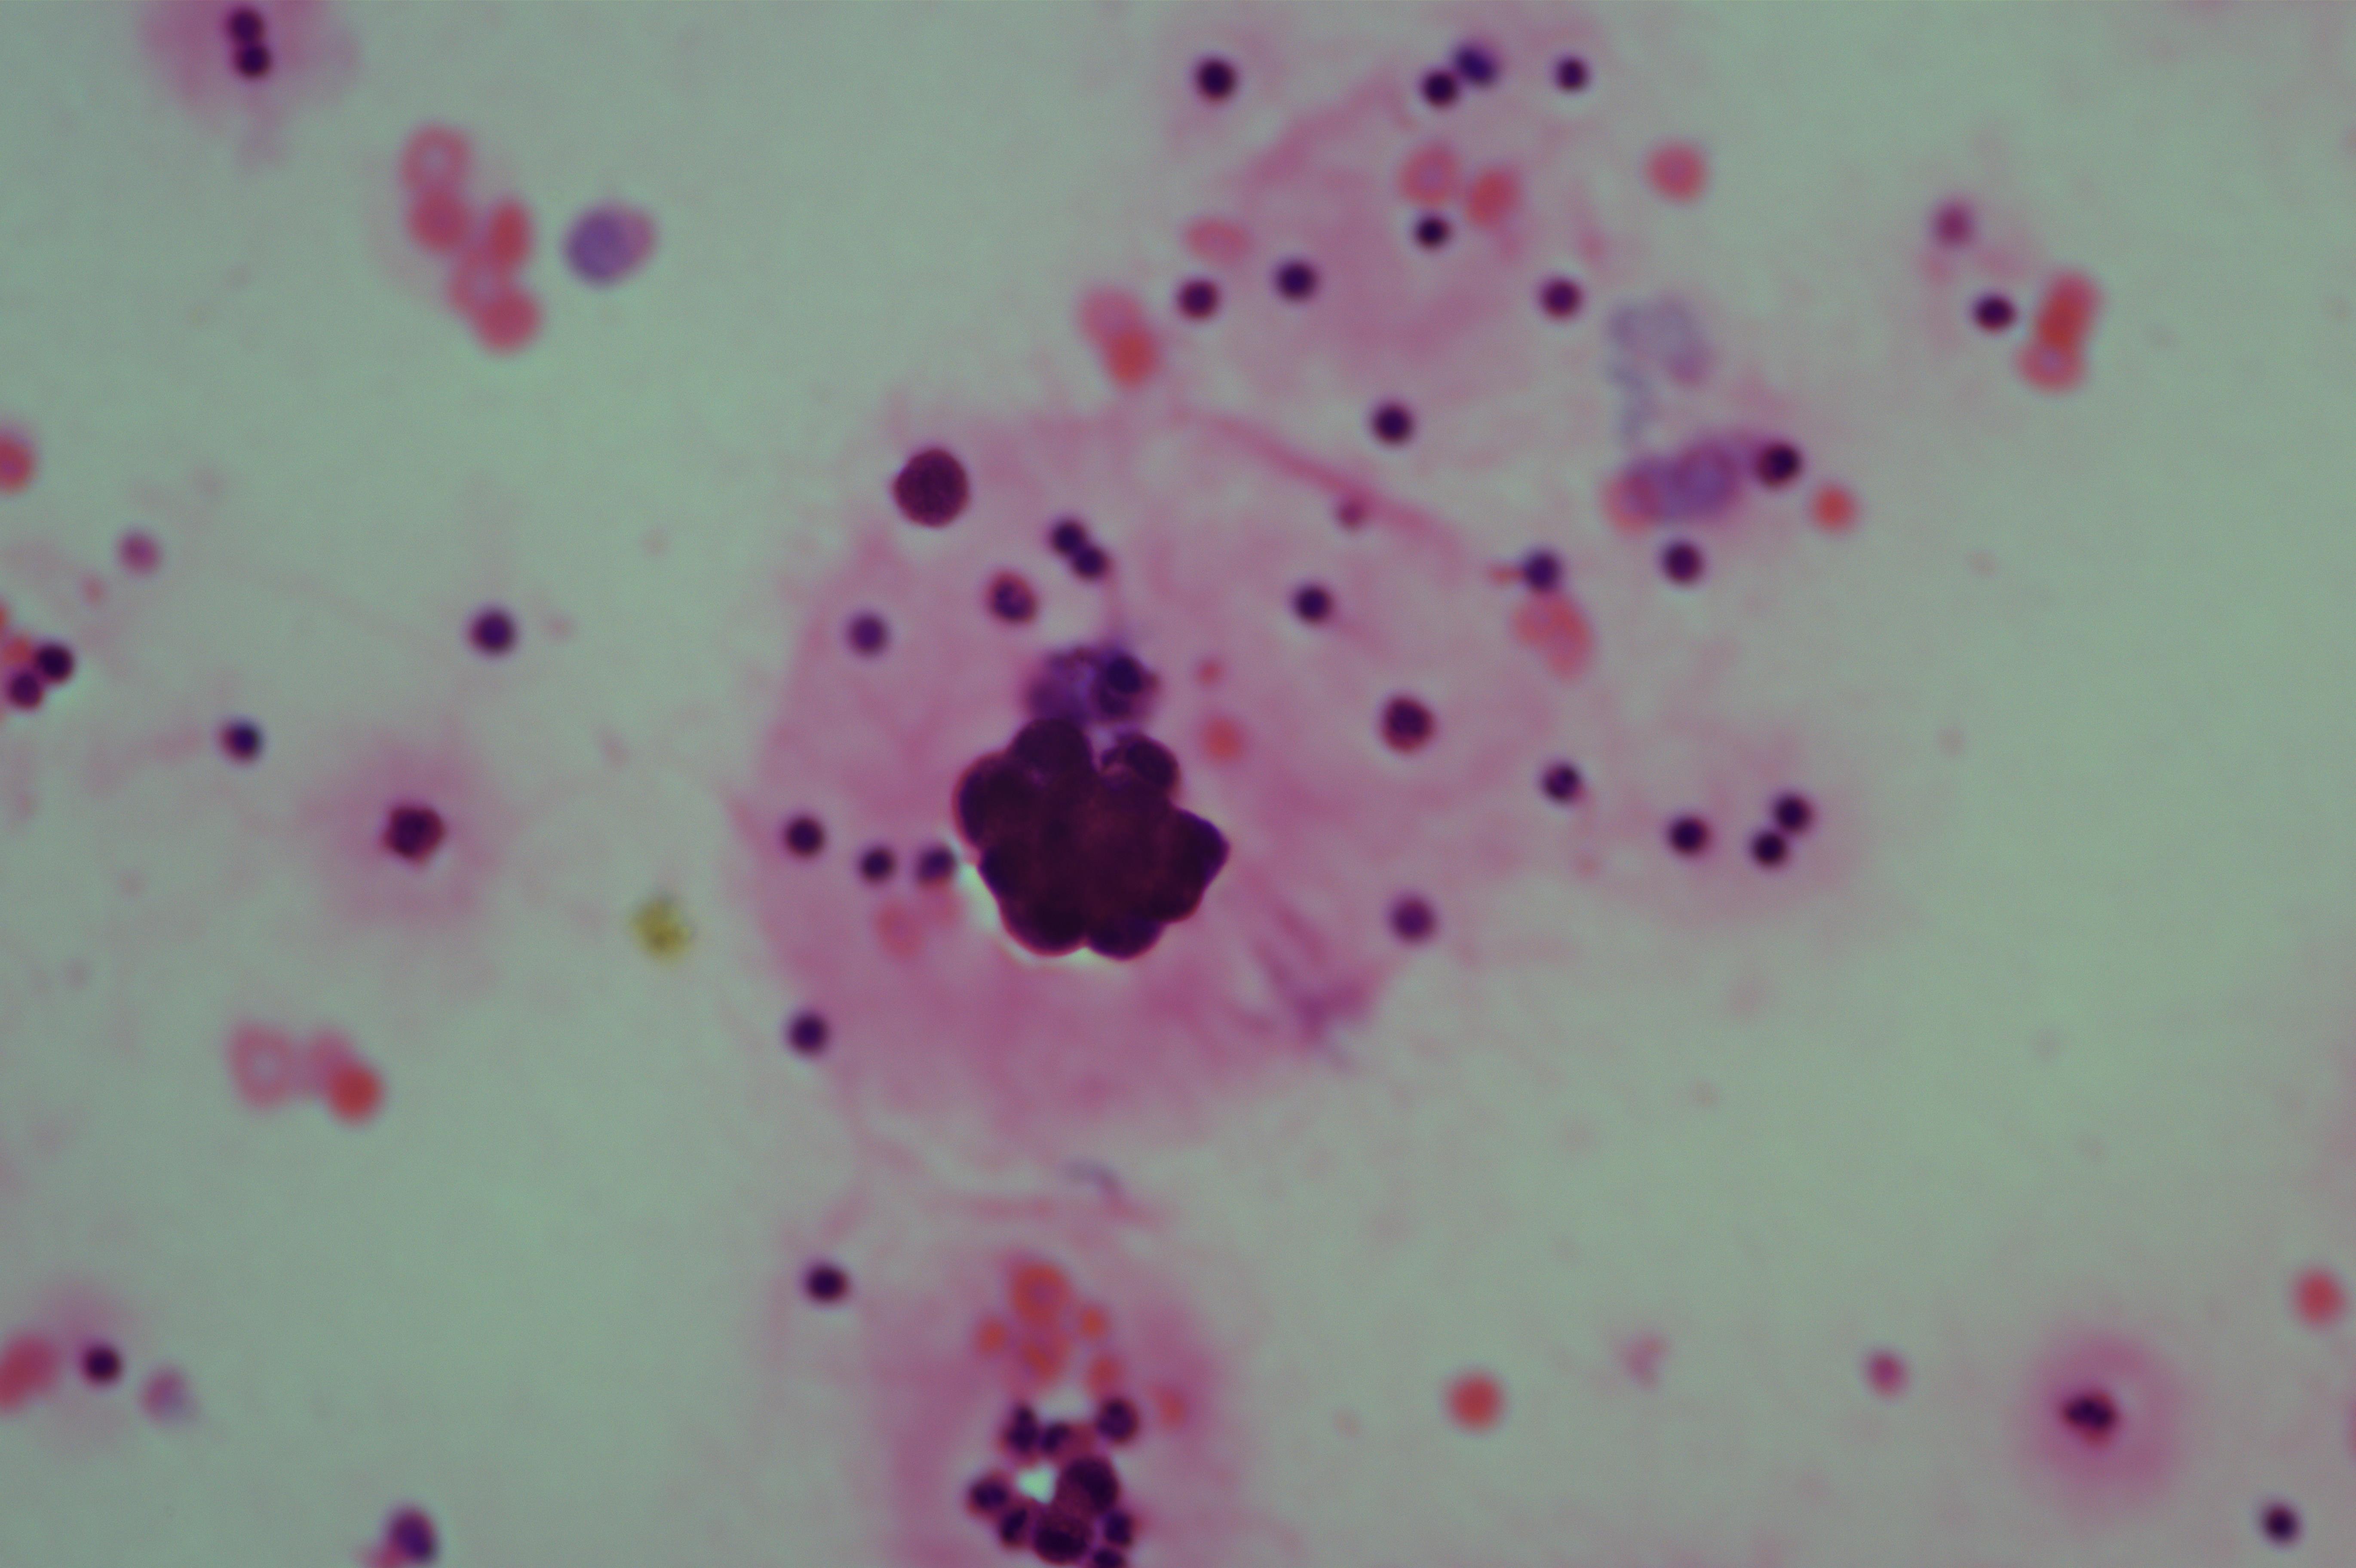

女,78岁,胸水腺癌

性别

女

年龄

78岁

一般病史

胃低分化腺癌术后一年

标本类型

胸水

制片方法

涂片

染色方法

HE

图2

考虑为腺癌

图3、图9是什么?